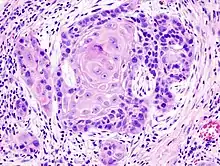

Cancer can be considered a very large and exceptionally heterogeneous family of malignant diseases, with squamous-cell carcinomas comprising one of the largest subsets.[17][18][19] All SCC lesions are thought to begin via the repeated, uncontrolled division of cancer stem cells of epithelial lineage or characteristics. SCCs arise from squamous cells, which are flat cells that line many areas of the body. Some of which are keratinocytes. Accumulation of these cancer cells causes a microscopic focus of abnormal cells that are, at least initially, locally confined within the specific tissue in which the progenitor cell resided. This condition is called squamous-cell carcinoma in situ, and it is diagnosed when the tumor has not yet penetrated the basement membrane or other delimiting structure to invade adjacent tissues. Once the lesion has grown and progressed to the point where it has breached, penetrated, and infiltrated adjacent structures, it is referred to as "invasive" squamous-cell carcinoma. Once a carcinoma becomes invasive, it is able to spread to other organs and cause the formation of a metastasis, or "secondary tumor".

One method of classifying squamous-cell carcinomas is by their appearance under microscope. Subtypes may include:

- adenoid squamous-cell carcinoma (also known as pseudoglandular squamous-cell carcinoma) is characterized by a tubular microscopic pattern and keratinocyte acantholysis.[22]